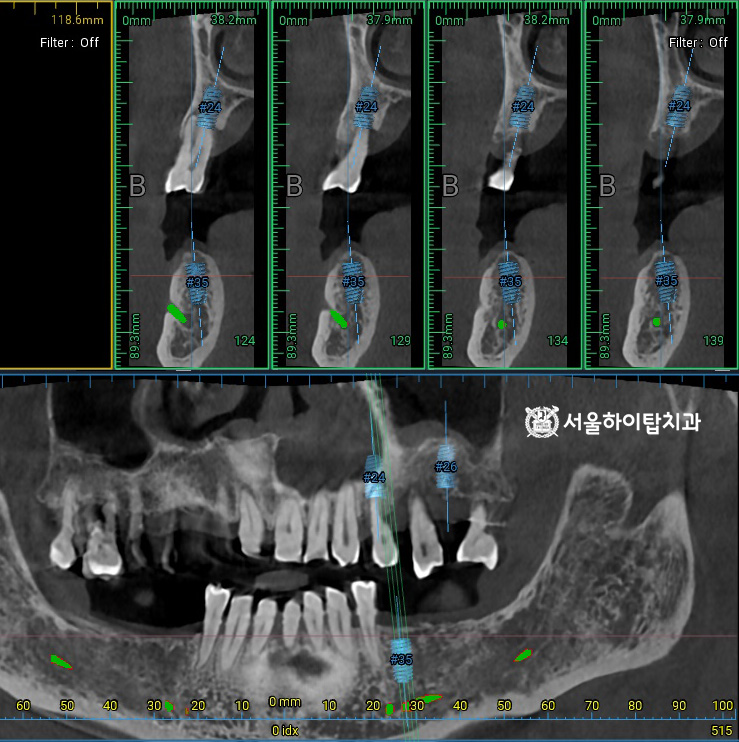

이와 함께, CT 촬영을 통해

픽스처가 식립될 위치를

사전에 시뮬레이션할 수 있습니다.

주안동 치과 에서는 이를 통해

잔존 치조골의 높이, 밀도, 두께,

해부학 구조물 등을 면밀히 분석하고,

시술 과정과 보철 설계를 정확하게

계획할 수 있다고 설명드립니다.